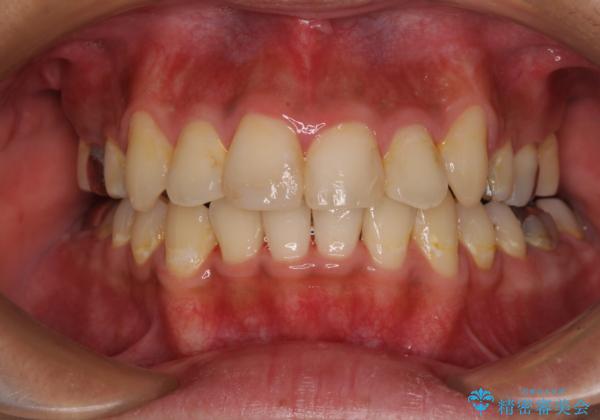

- 前歯のデコボコと八重歯、開咬を気にして来院された患者様です。

骨格的に下顎骨が上顎骨に対して後退位であったため、上顎の左右第一小臼歯を抜歯し、デコボコを改善するとともに開咬を改善していくこととしました。

自己管理が煩わしいとのことで、表側のワイヤー装置にて治療を進めて行くこととしました。